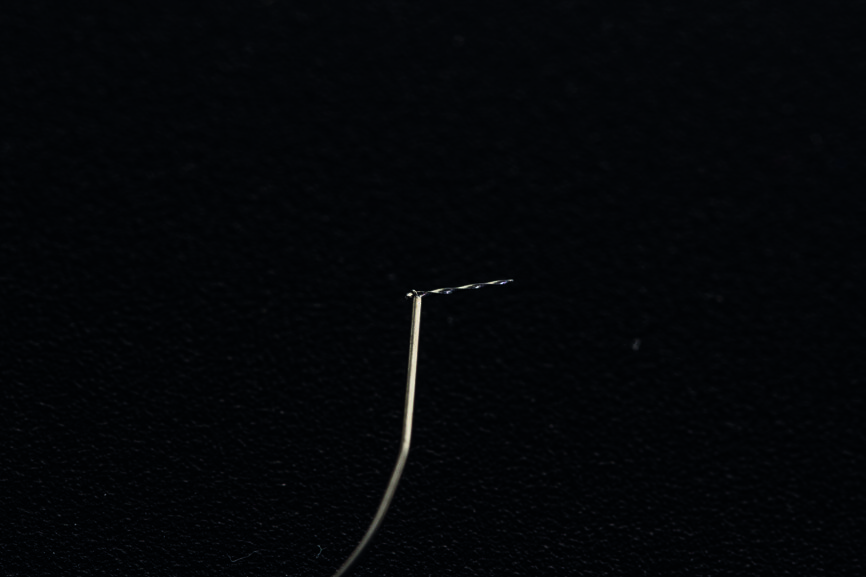

Fig. 2 : Lime Micro Type D à utiliser avec SONICflex 2003 L et adaptateur OSADA.

Fig. 3 : Fraise Gates–Glidden modifiée de taille 3 (modification d’une fraise Gates–Glidden avec une fraise à pointe diamantée).